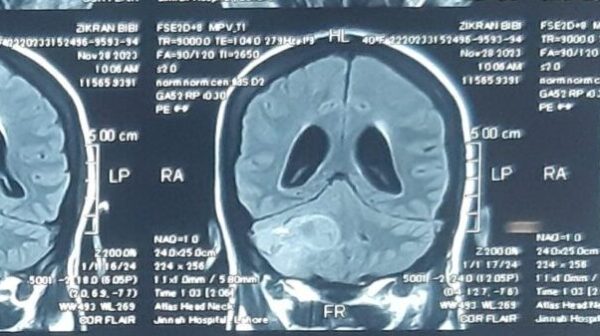

The Neurosurgery Department of AIMC/ Jinnah Hospital Lahore is a leading center for neurosurgical patient care, postgraduate training and research. Allama Iqbal Medical College and its affiliated teaching Jinnah Hospital is a very well recognized medical school of the country. It’s Department of Neurosurgery has emerged to be a leading center of excellence in a very short span of time.

Yes, Once admitted almost all facilities will be available under one roof starting from the investigations like CT Scan CT angiogram, MRI, MRA, laboratory studies etc. There is a highly specialized, Neuro critical care unit in case the patient needs it. The Department is equipped with state-of-the-art facilities and has one of the most advanced operation theatres complex available internationally.